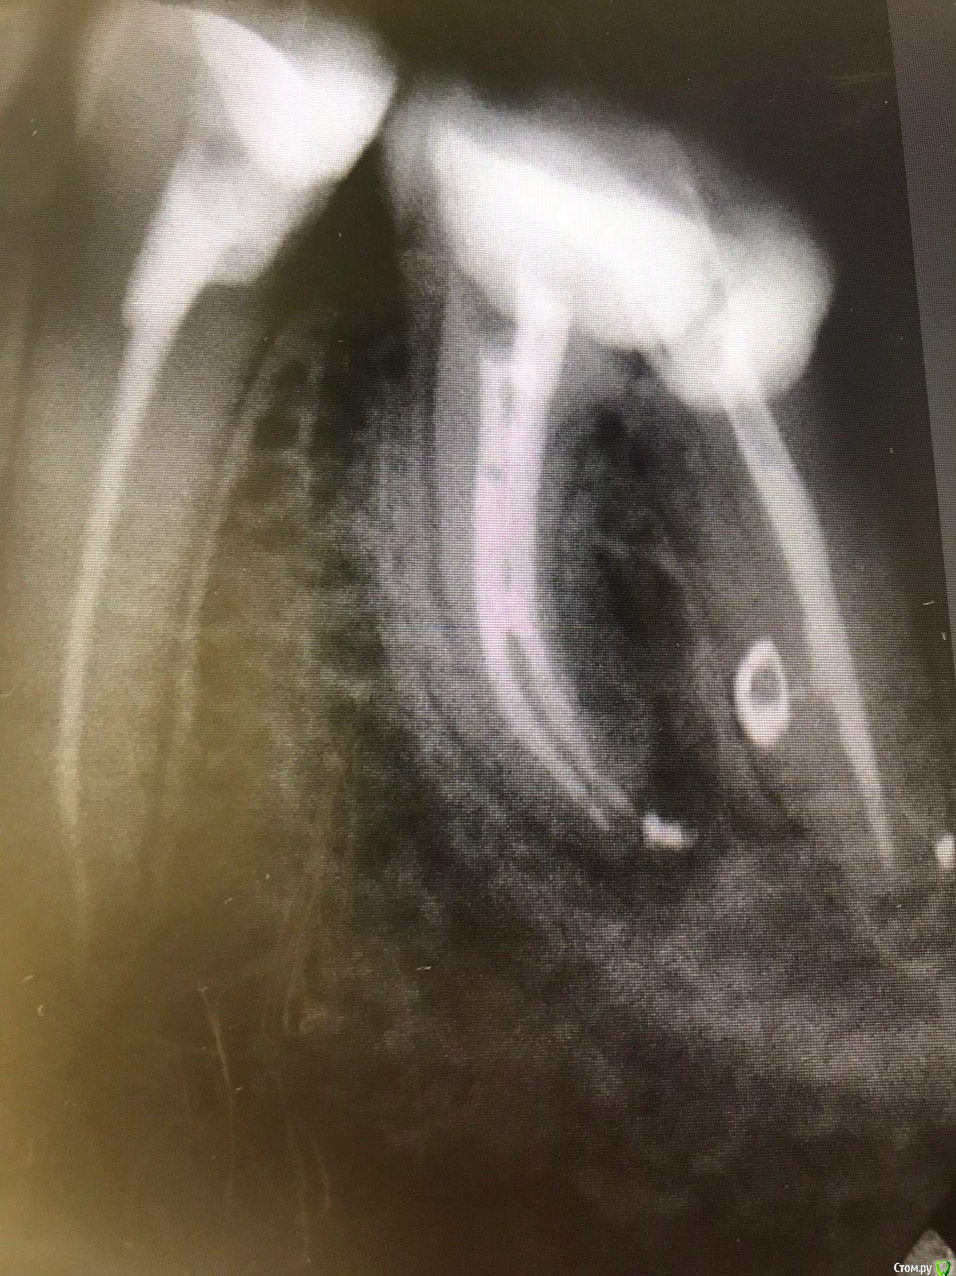

1586Doc Опубликовано 10 февраля, 2020 Автор Поделиться Опубликовано 10 февраля, 2020 (изменено) А где контроль на сегодня? При таком качестве снимков оценить будет тяжело.первые 2 фото снимки 9 месяц назад, до ревизии Изменено 10 февраля, 2020 пользователем 1586Doc Ссылка на комментарий

Паращук Роман Опубликовано 10 февраля, 2020 Поделиться Опубликовано 10 февраля, 2020 первые 2 фото снимки 9 месяц ранее до ревизии Имхо пока не вижу успеха. (( Ссылка на комментарий

1586Doc Опубликовано 10 февраля, 2020 Автор Поделиться Опубликовано 10 февраля, 2020 (изменено) Имхо пока не вижу успеха. ((ну если еще с 46 я могу понять, 45 явно деструкция в разы меньше. 100% месяца через 3-4 назначу клкт Изменено 10 февраля, 2020 пользователем 1586Doc Ссылка на комментарий